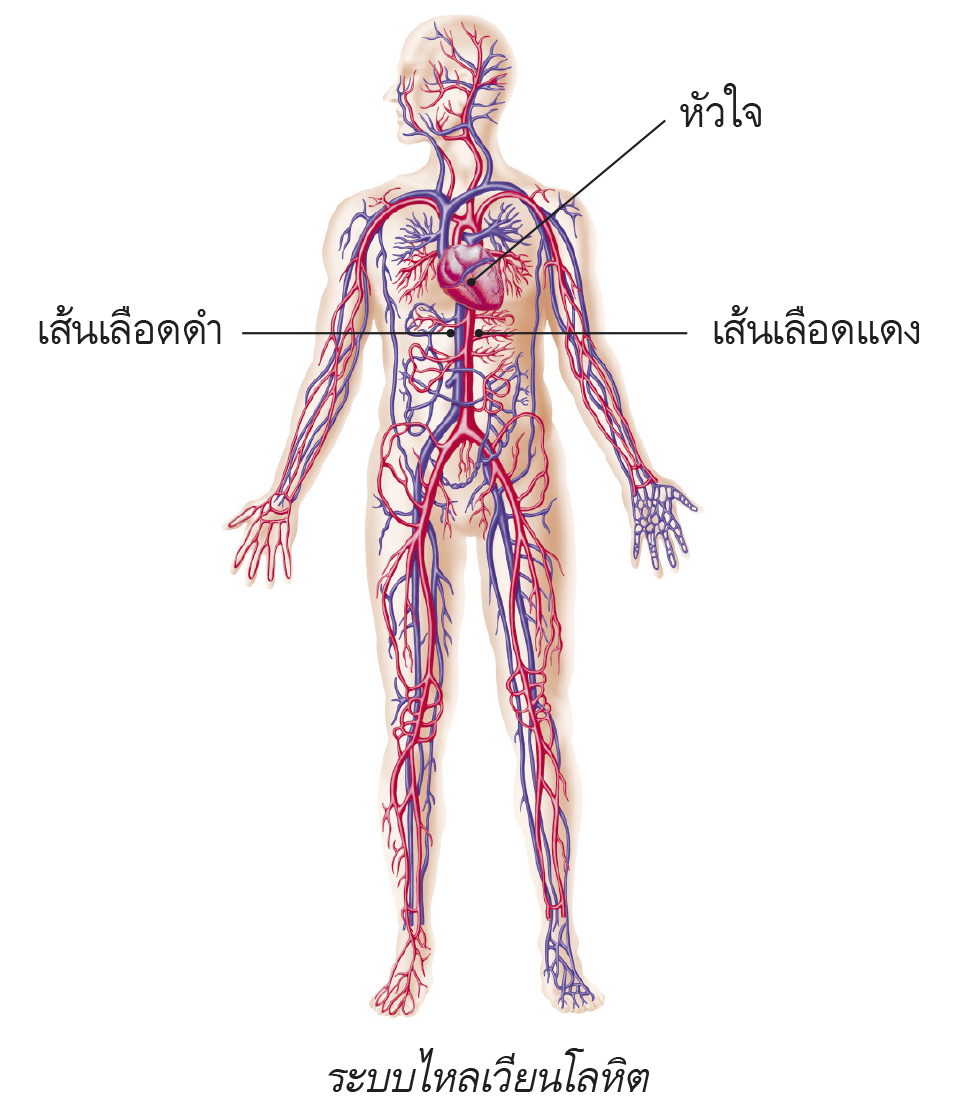

รูประบบไหลเวียนโลหิต

ระบบไหลเวียนโลหิต ทำหน้าที่อะไร และมีส่วนประกอบสำคัญอะไรบ้าง

ระบบไหลเวียนโลหิต ทำหน้าที่อะไร และมีส่วนประกอบสำคัญอะไรบ้าง 269,300+ ระบบหายใจ ระบบไหลเวียนโลหิต ภาพถ่ายสต็อก รูปภาพ และภาพปลอดค่า …

หลอดเลือดแดงและระบบไหลเวียนโลหิตของมนุษย์และกายวิภาคของหลอดเลือดดํา ภาพ … ระบบไหลเวียนโลหิต #EP-515

หลอดเลือดในร่างกายมี 3 ชนิด แสดงแบบจำลองกายวิภาคศาสตร์การไหลเวียนโลหิตรวมถึงระบบหัวใจและหลอดเลือด …